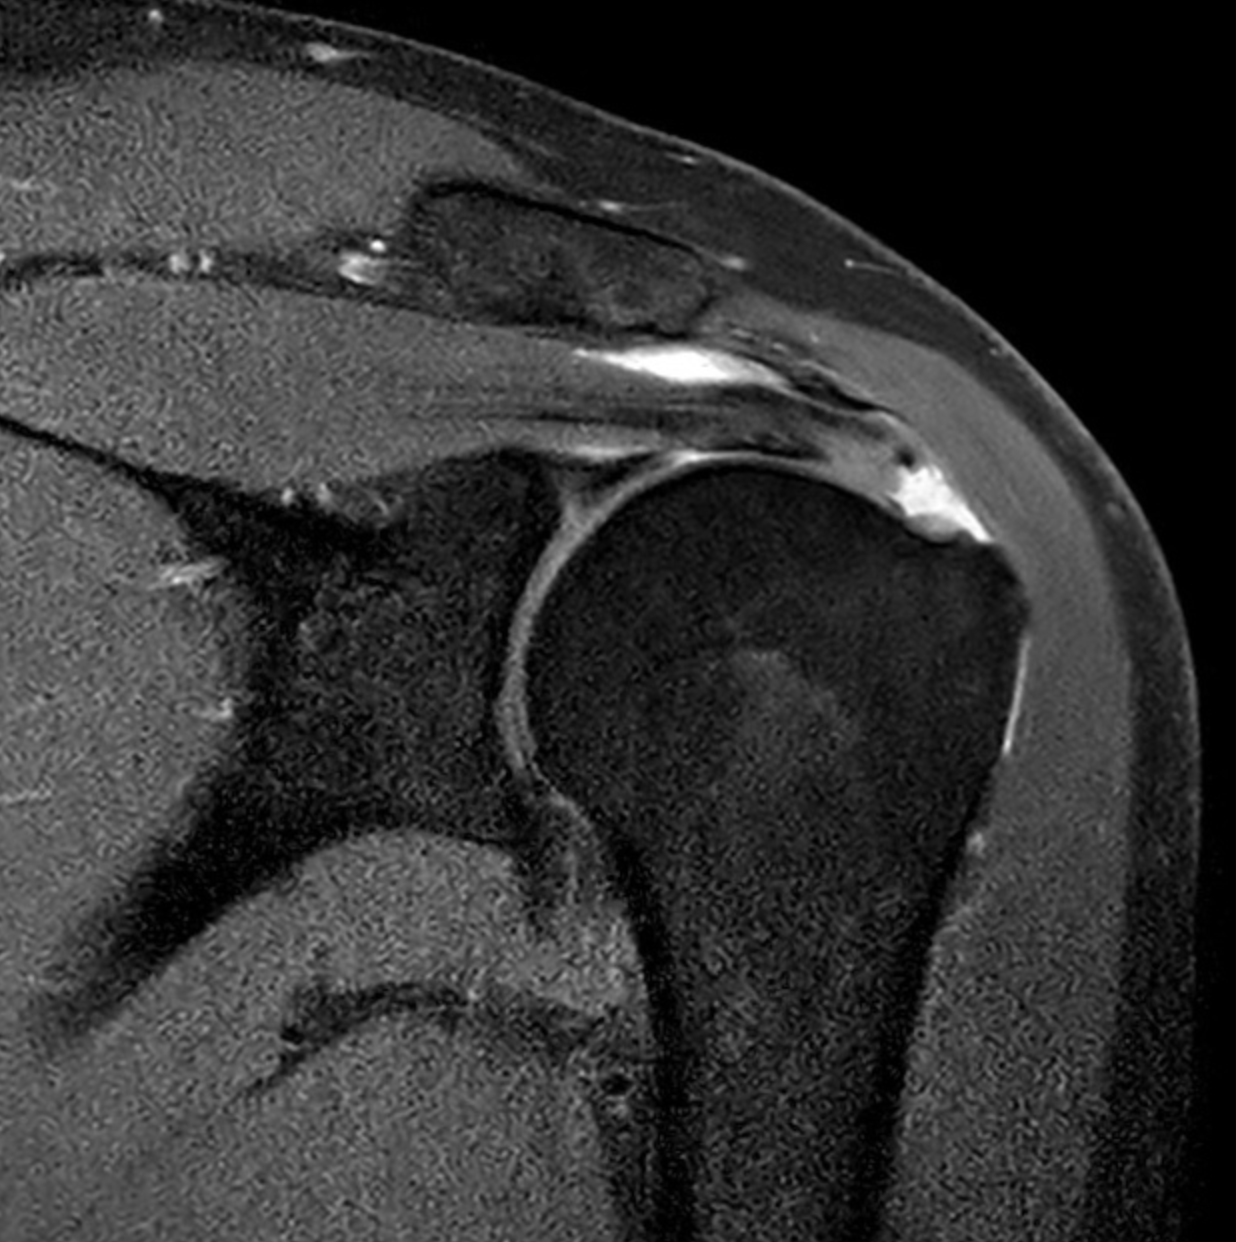

Rotator Cuff Tear

A rotator cuff tear occurs when one or more of the tendons responsible for stabilising the shoulder become partially or completely torn.

This injury can result from acute trauma or develop gradually due to chronic wear and degeneration.